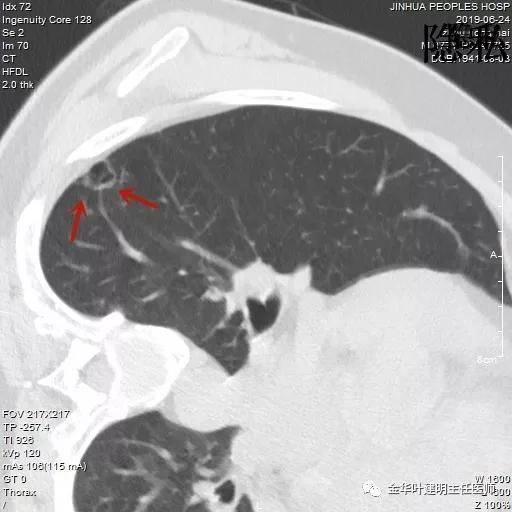

可见其右下叶有一空腔性病灶,壁薄,病灶下方见到实性密度的成份。我们看过目前的片子后,马上想到的是此病灶以前有没有,对比是非常重要的。调出之前片子: